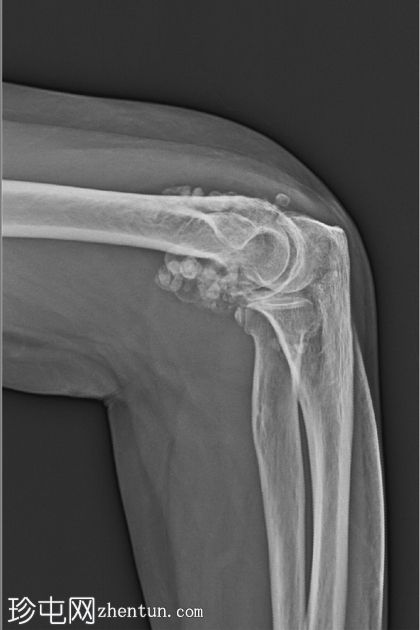

2.jpeg

侧面

肘关节内多个边界清晰的钙化/骨化游离体,主要位于前后凹处。关节面不规则、骨赘形成、关节间隙狭窄以及肱骨远端、尺骨近端和桡骨头的软骨下硬化均符合骨关节炎的改变。桡骨头轮廓不规则,并有一条模糊的硬化线,提示为陈旧性愈合骨折。无急性骨折或脱位。